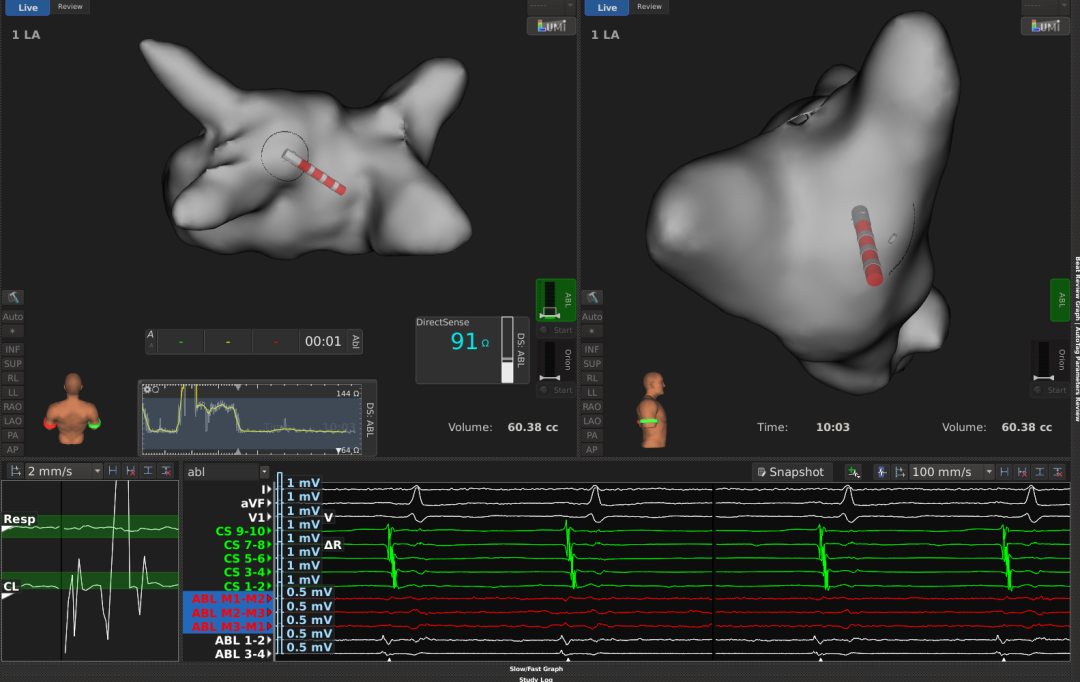

近日,南京大学医学院附属鼓楼医院心内科徐伟主任团队沈文志博士成功完成了首台基于DIRECTSENSE局部阻抗监测技术的阵发性房颤高功率射频消融手术。作为房颤射频消融手术的新型诊疗工具,该技术通过配合RHYTHMIA HDx™心脏电生理三维标测系统和INTELLANAV MiFi OI磁定位微电极盐水灌注消融导管,可在手术过程中监测局部阻抗变化,助力医者对导管贴靠和消融状况进行实时评估、获取心肌组织真实消融反馈,从而优化诊疗手术方案,满足患者多样化的疾病诊疗需求。

2.左房建模:用有64个单面印刷微电极的三维标测导管Orion建立完整的左房模型,建模的同时完成高密度电信号采集与标测。沈文志主任表示,因Orion导管的电极采用单面印刷工艺及其足够小的电极面积(0.4mm²),更能保证所采集的电信号清晰度,可以更好的反应真实的心肌电压及疾病机制。

血池中基础阻抗:91Ω左右

3.消融策略:因LPV和RPV肺静脉均有电传导,故决定行环肺静脉隔离(PVI), 本次PVI消融终点:消融中电位明显下降;orion网篮导管,LPV和RPV均阻滞。

4.消融过程示例:导管位于RIPV,贴靠稳定后初始阻抗约125Ω(较血池阻抗上升34Ω,电位明显,贴靠度良好),放电过程中,微电极上电位下降明显,阻抗下降33Ω,后稳定在平台期。

2.LI曲线的波动也一定程度上提示我们贴靠情况,阻抗基于血池中初始阻抗增加20Ω左右且曲线重合度高,可考虑为贴靠良好,但也需要结合电位来判断。

术中设置导管头端在半径5mm范围内稳定3秒,且局部阻抗LI下降4Ω及以上可自动取点

局部阻抗LI下降<10Ω为浅色点,≥15Ω为深色点,10-15Ω为中等颜色。